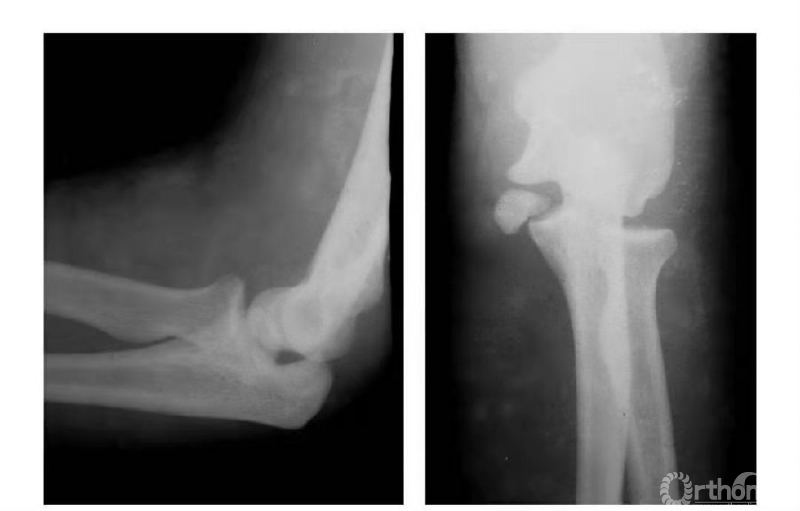

一、新鲜性内髁骨折

本病多见成年患者。

例1:肱骨内髁骨折,折线由滑车外缘沿鹰嘴窝上缘,并呈直角状而拐向内上髁(属于稳定型)(图1)。

图1

例2:肱骨内髁骨折,折线经滑车外缘斜向内髁上部(非稳定型)(图2)。

图2

例3:肱骨内髁长斜形劈裂骨折(折线长约10cm)(图3)。

图3